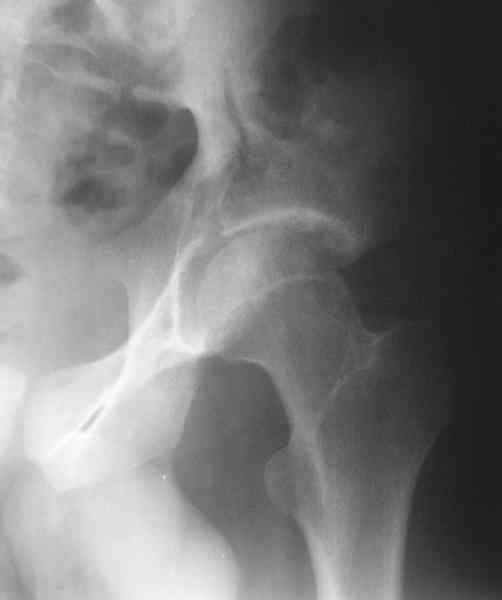

Нелеченный перелом вертлужной впадины

Мужчина 33 лет получил травму в шахте (придавило вагонеткой) 6 недель назад. Изолированное повреждение вертлужной впадины.

В местной больнице отлежал несколько недель на вытяжении. После выписки амбулатрный травматолог направил в институт. На сегодня, похоже, уже имеется неправиильное сращение. См. картинки.

Вопрос - что делать сейчас? Оставить как есть или идти на открытое восстановление? Если последнее, то какой доступ, репозиционные манипуляции и фиксацию тут можно посоветовать? Заранее спасибо.

Dear all, A male 23 y.o. injured 6 weeks ago - mine trauma, impacted by a carriage. Isolated injury of the acetabulum. At the initial hosptial was on bed traction some weeks. After discharge visited anotheк orthopaedic surgeon who referred him to our unit. To date looks like a malunion. Images attached. The question is about what to do now - either leave it as is or perform open reduction? If the latter what approach, reduction manoeuvres and fixation would you advice? Thx in advance!